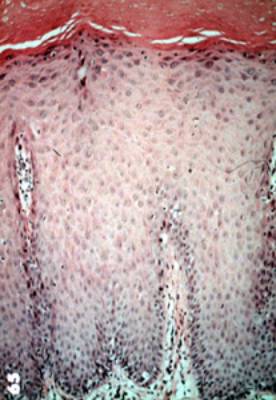

Con más aumento,

la displasia muestra queratina en la superficie, agrandamiento de los núcleos,

variación en la cantidad del citoplasma, variación en la morfología y

tamaño nuclear, desorientación en la capa celular basal y

queratinización prematura y degeneración celular. |

Para repasar la diferencia entre el

epitelio normal y epitelio displásico usted debe comparar esta imagen

que es normal con la imagen anterior. |